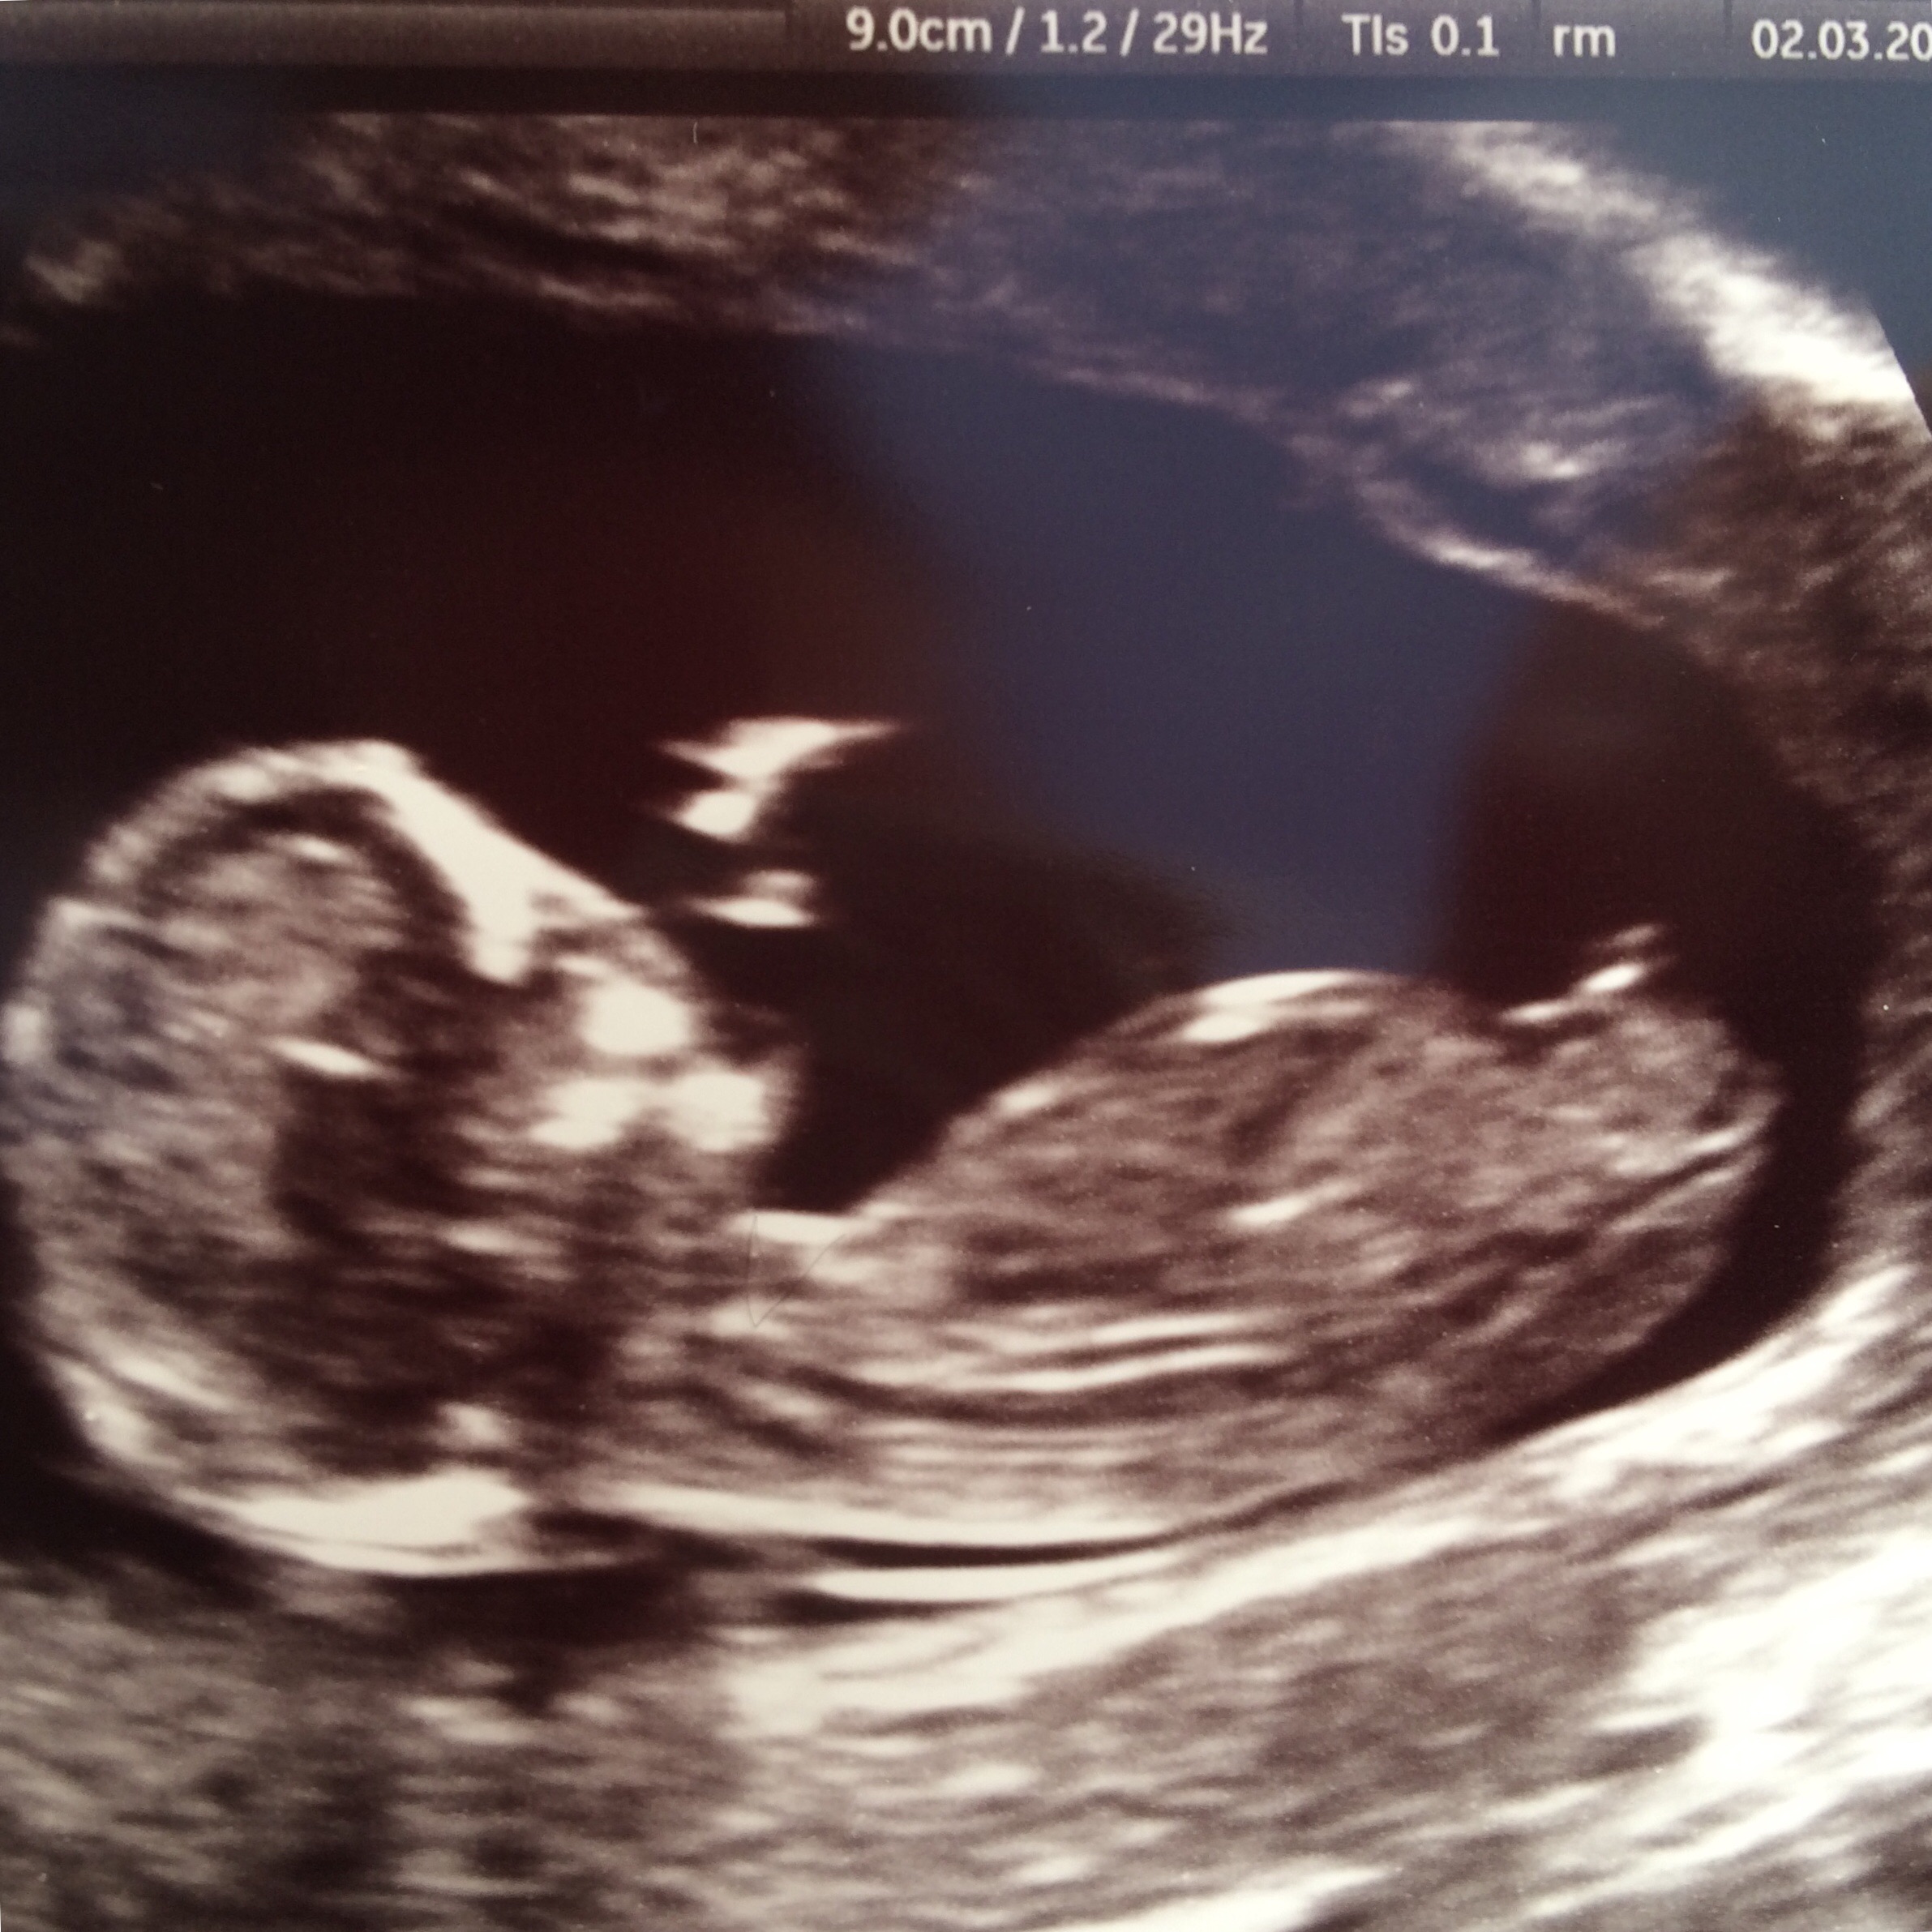

Guesses please! XxAttachment 24208Attachment 24209

12+3 is early, but to me it looks girly. I've seen lots of stacked nubs that have ended up being girls so to me that's not what indicates gender, I look more at the angle of the nub, which in your pics is very parallel to the spine which makes me say girl.

This is a tricky one. On the first two it's short and stacked (boy) but on the last picture it's longer and parallell to the spine and forked (girl).

I see a girl. The bladder is right behind the nub and the nub looks long and flat. Unsure whether that’s stacking in the first 2 pics but I’m guessing girl.